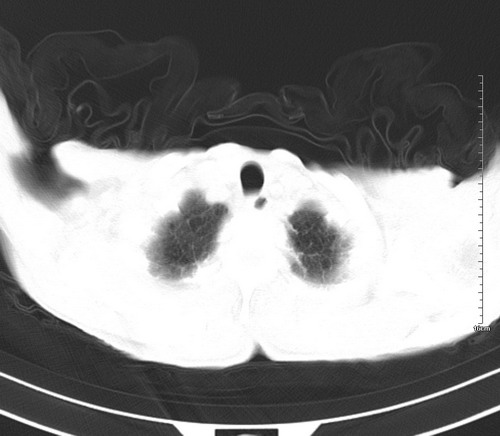

中后纵隔占位,气管、食道受压、变形、移位。恶性可能性大。

考虑:中后纵隔转移瘤可能性大,主动脉硬化。

中后纵隔占位, 考虑:转移瘤不除外.

纵隔淋巴结肿大,考虑转移而来

后中纵隔团块影,伴气管、食道受压移位,首先考虑转移瘤,肝s5段低密度灶。建议增强检查,另外其结肠是否有问题请提供,右肺部分肺叶局限含气增多,考虑局限肺气肿。

建议强化检查,考虑纵隔型肺癌,小细胞可能性大。

后中纵隔淋巴结肿大,首先考虑转移瘤。